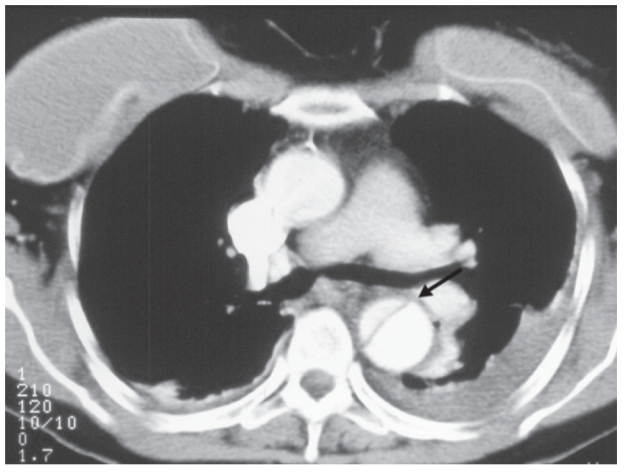

A 57-year-old female sociology student presented to the emergency department with 5–6 days history of persistent epigastric pain radiating to the interscapular region. She had past history of poorly controlled hypertension with no history of a collagen vascular disorder. Previously she had burr-hole evacuation of a traumatic acute subdural hematoma in 1998, with good recovery. Her hemodynamic parameters were stable on admission with a blood pressure of 145/70 mmHg in the right arm and 146/70 in the left. Air entry was reduced in the left lung base. Her hemoglobin was 9.8 gm/dl with a serum creatinine of 61 mmol/L and lactate of 1.2 mmol/L. Both the femoral pulses were palpable and there was no evidence of myocardial ischemia on electrocardiogram. Chest radiograph showed left basal fluid and an urgent computer tomography (CT) scan identified a type B dissection of the thoracic aorta extending down to the abdominal aorta with an exit point of dissection in the right external iliac artery (EIA). Blood flow was seen in both the true and false lumens (Figure 1) with the right kidney being perfused by the false lumen. A decision to stent-graft the thoracic dissection was made in view of her persistent chest pain. Despite her relatively young age, the option of open surgical repair was not considered because of the higher mortality associated with surgery.

Figure 1.

Computerized tomography scan showing a type B dissection of the descending thoracic aorta with true and false lumens (arrow).